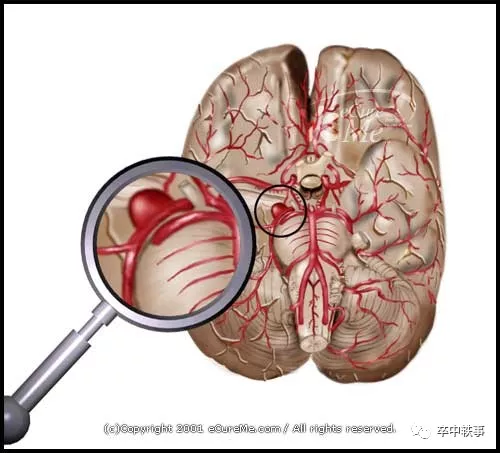

从1990年起人们可以介入栓塞颅内动脉瘤了 (上图)。开刀夹闭动脉瘤手术越来越少了。